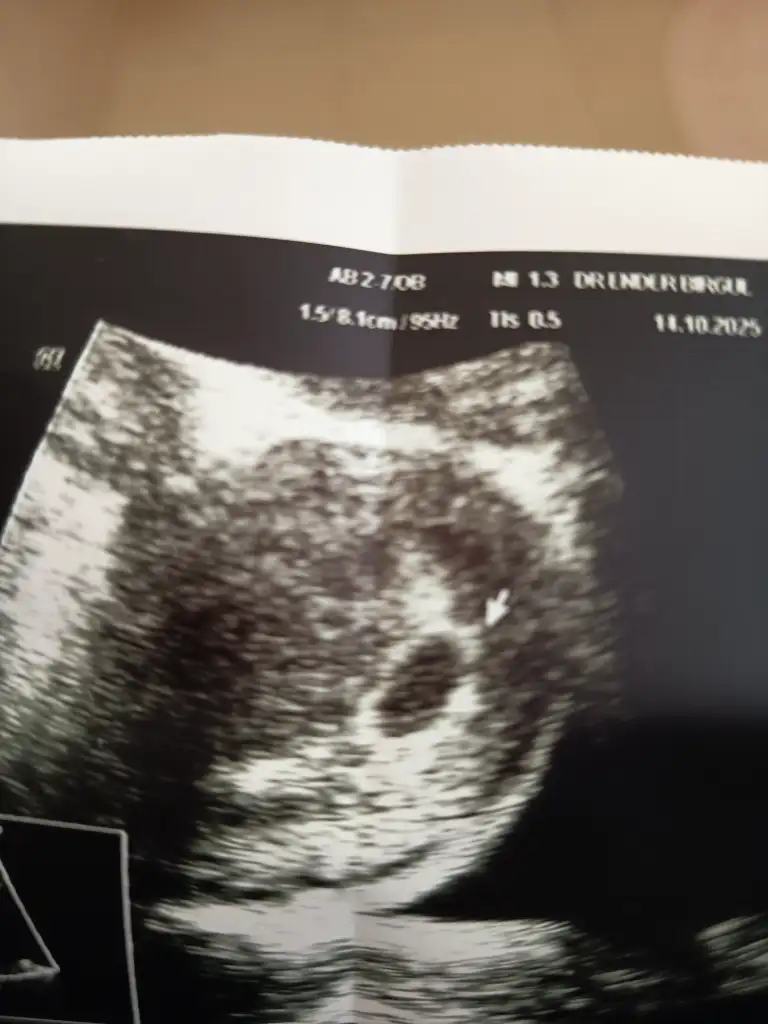

Mrb canım dün biraz agrım oldu diye acile gittim korkup sence kesem de gelişme varmı ilk zamana göre bakabilir misin 5+2Aynen öyle canım haftaya perşembe dimi randevun